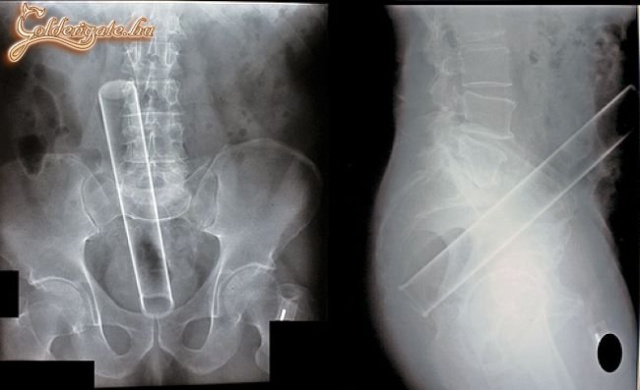

Valahol távolkeleten történt, hogy egy robogón ment két srác. Elöttük ment egy teherautó, amely vascsőveket szállított. Megcsúszott a rakomány, és két cső egyszerre szúrta át a két srácot. Hosszú ideig ott szerencsétlenkedtek a mentősök, amíg sikerült őket a szétválasztani, és mentőbe rakni a 6 m-es csővekre felfűzött fiúkat. Túlélték az esetet.

Abból ítélve, hogy kilóg a felső része a hasfalból, gyanítom, hogy nem játszadozás közbeni baleset!

ez sztem előlről ment be